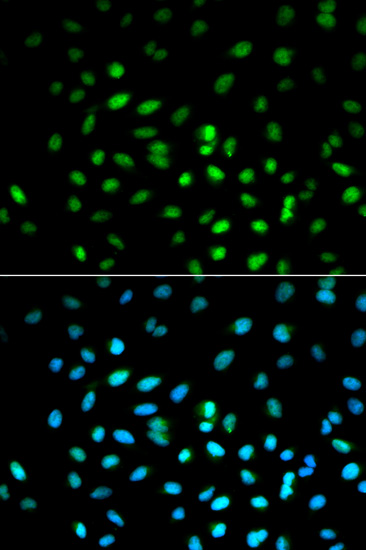

Immunofluorescence analysis of MCF7 cell using STK11 antibody. Blue: DAPI for nuclear staining.